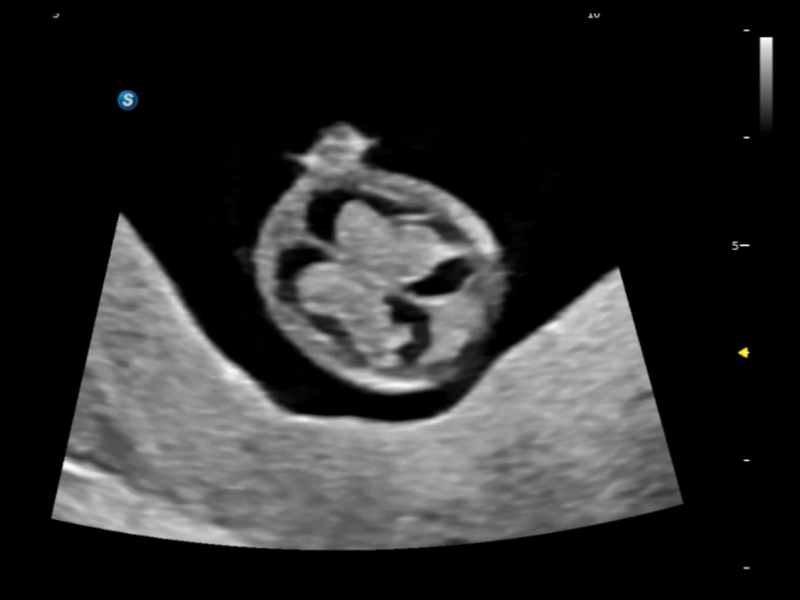

作為開立醫(yī)療全新打造的超高端旗艦超聲產(chǎn)品,從探頭抬起喚醒開啟掃查到多維探頭發(fā)射接收,通過先進(jìn)的場(chǎng)成像發(fā)射、自適應(yīng)聚合重建等技術(shù),基于RF Data原始射頻數(shù)據(jù)在圖像生成、高端功能等方面實(shí)現(xiàn)突破,為婦產(chǎn)科、兒科提供全方位臨床解決方案。

豐富的血流動(dòng)力學(xué)檢測(cè)技術(shù),可在不同醫(yī)療場(chǎng)景中高效捕捉血流信號(hào),助力臨床診療。

在傳統(tǒng)血流的基礎(chǔ)上優(yōu)化掃查和算法策略,能夠更好的抑制組織信息,提煉紅細(xì)胞運(yùn)動(dòng)信息,得到更高幀頻,高靈敏度和分辨率的血流信號(hào),還原更真實(shí)的血流動(dòng)力學(xué)。